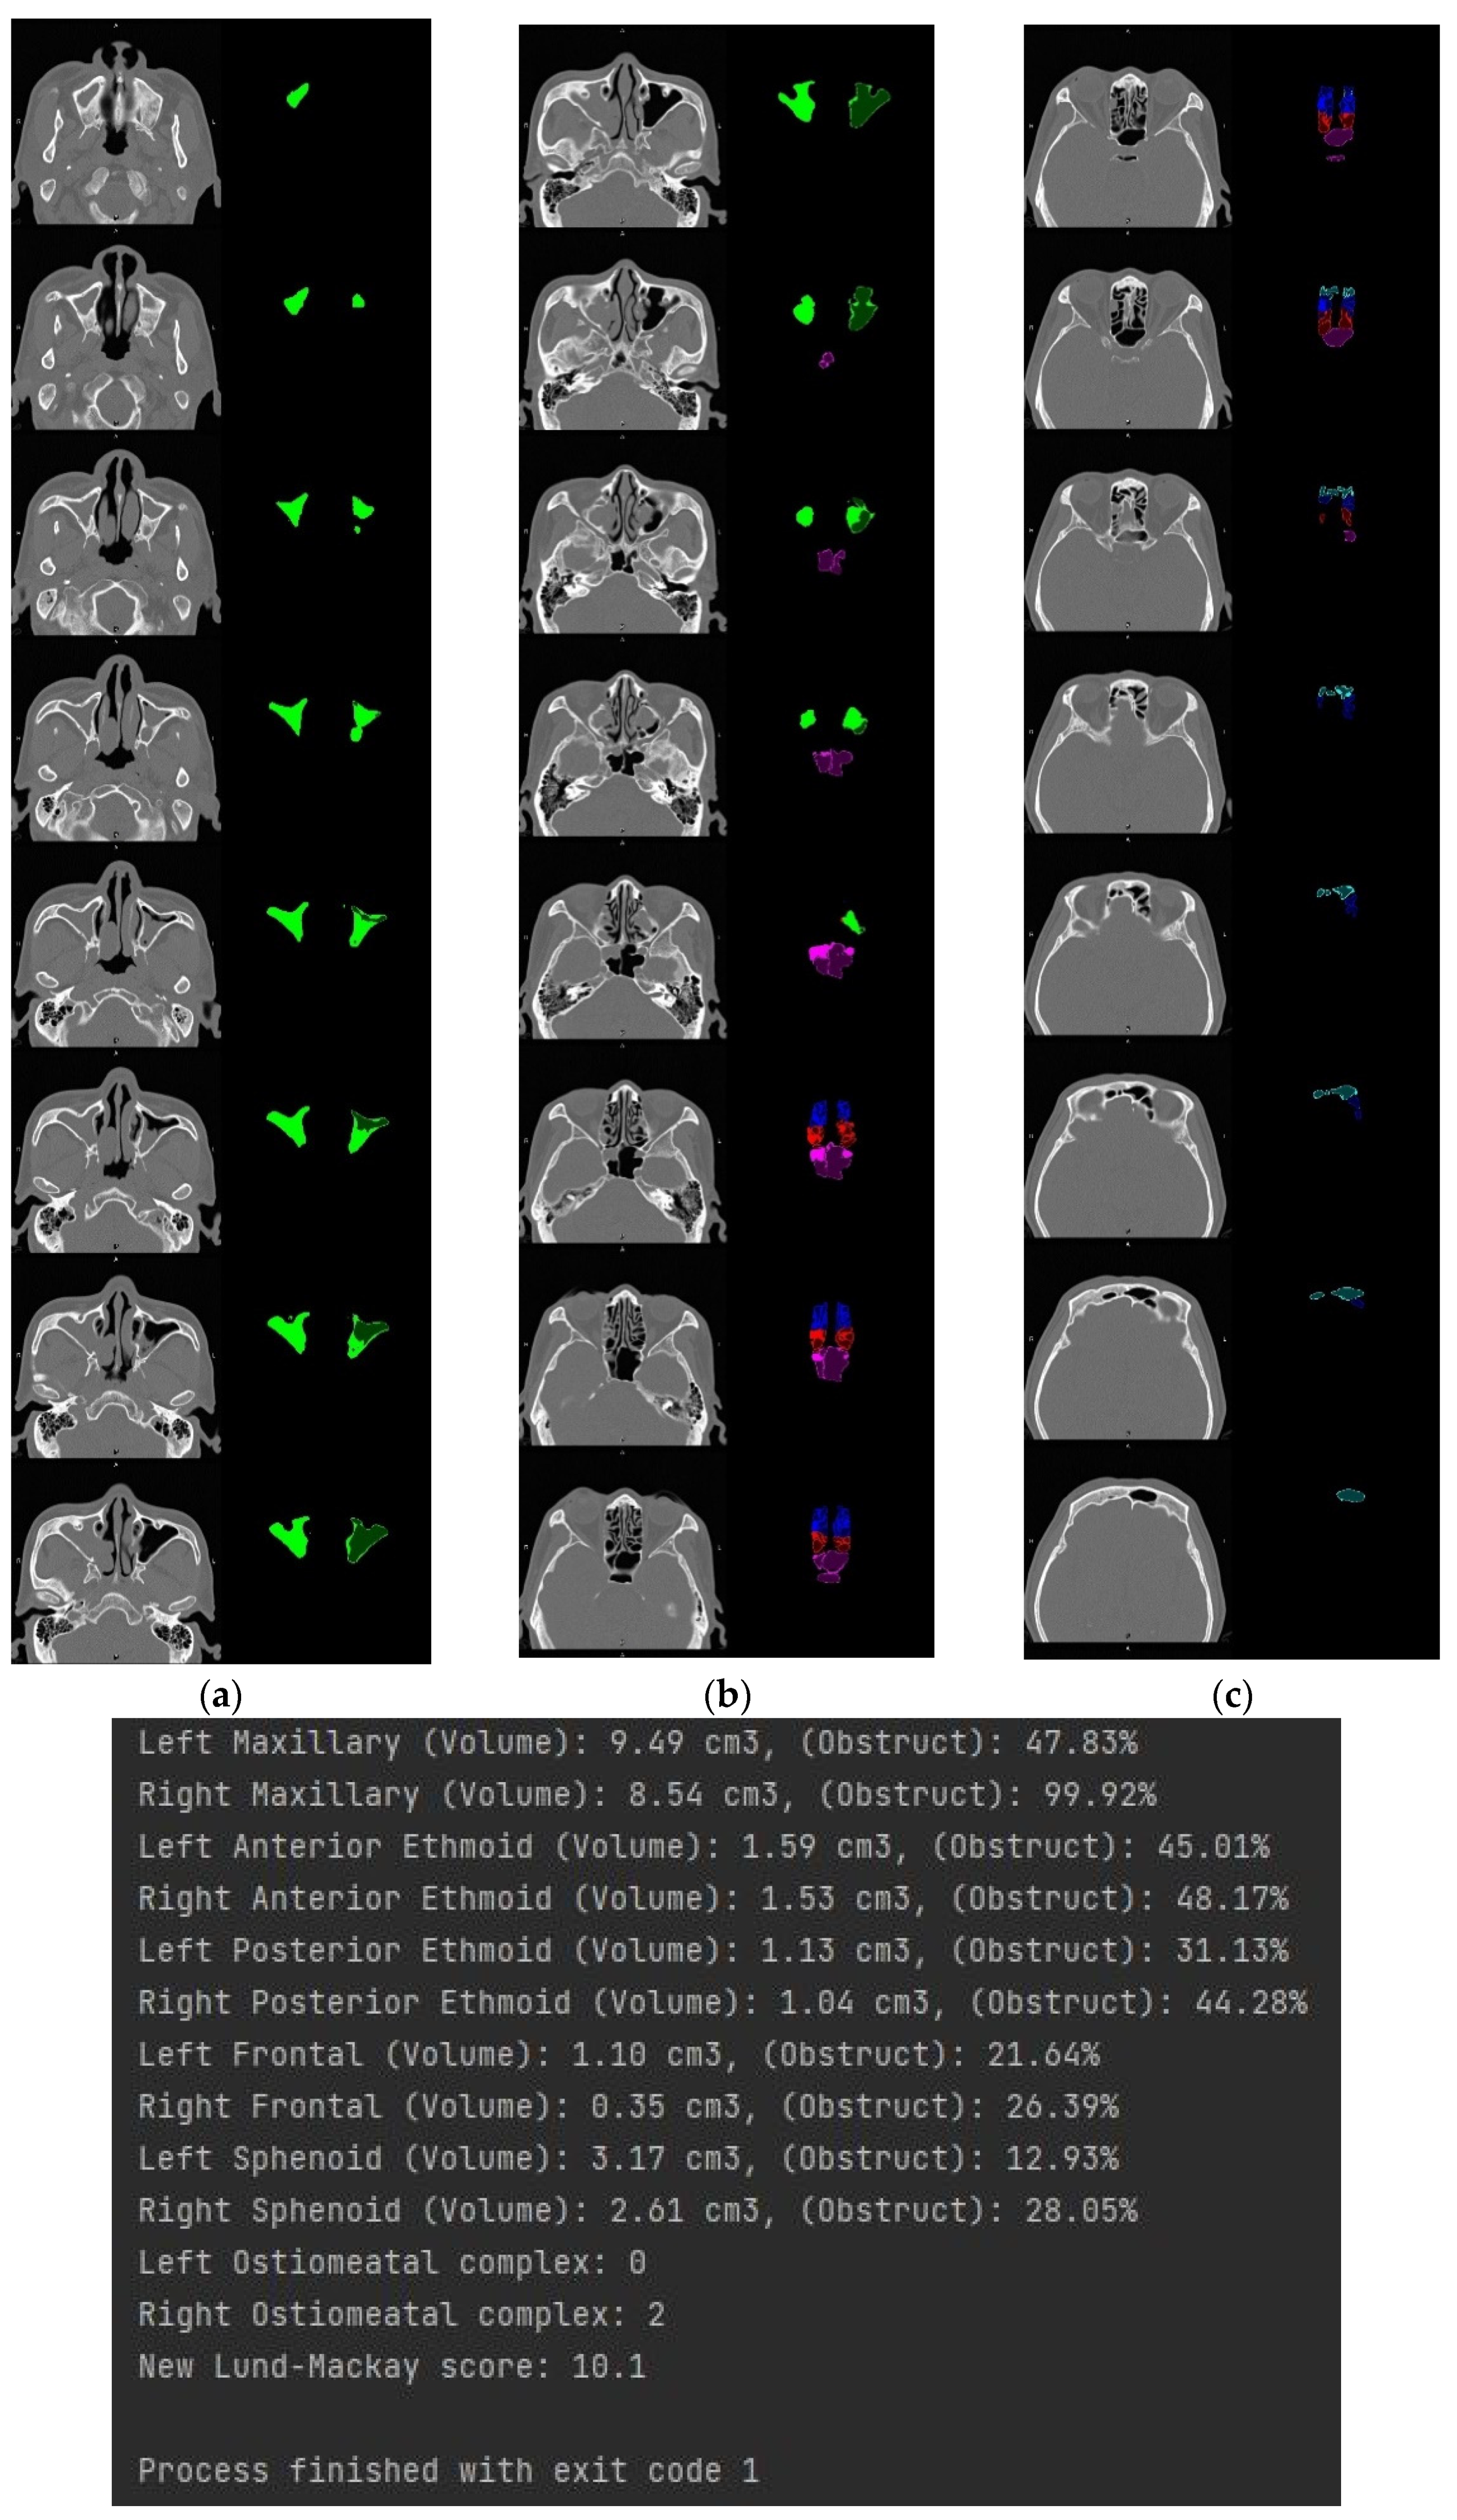

3.4. Volume Reconstruction

3.4.2. 3D Reconstruction